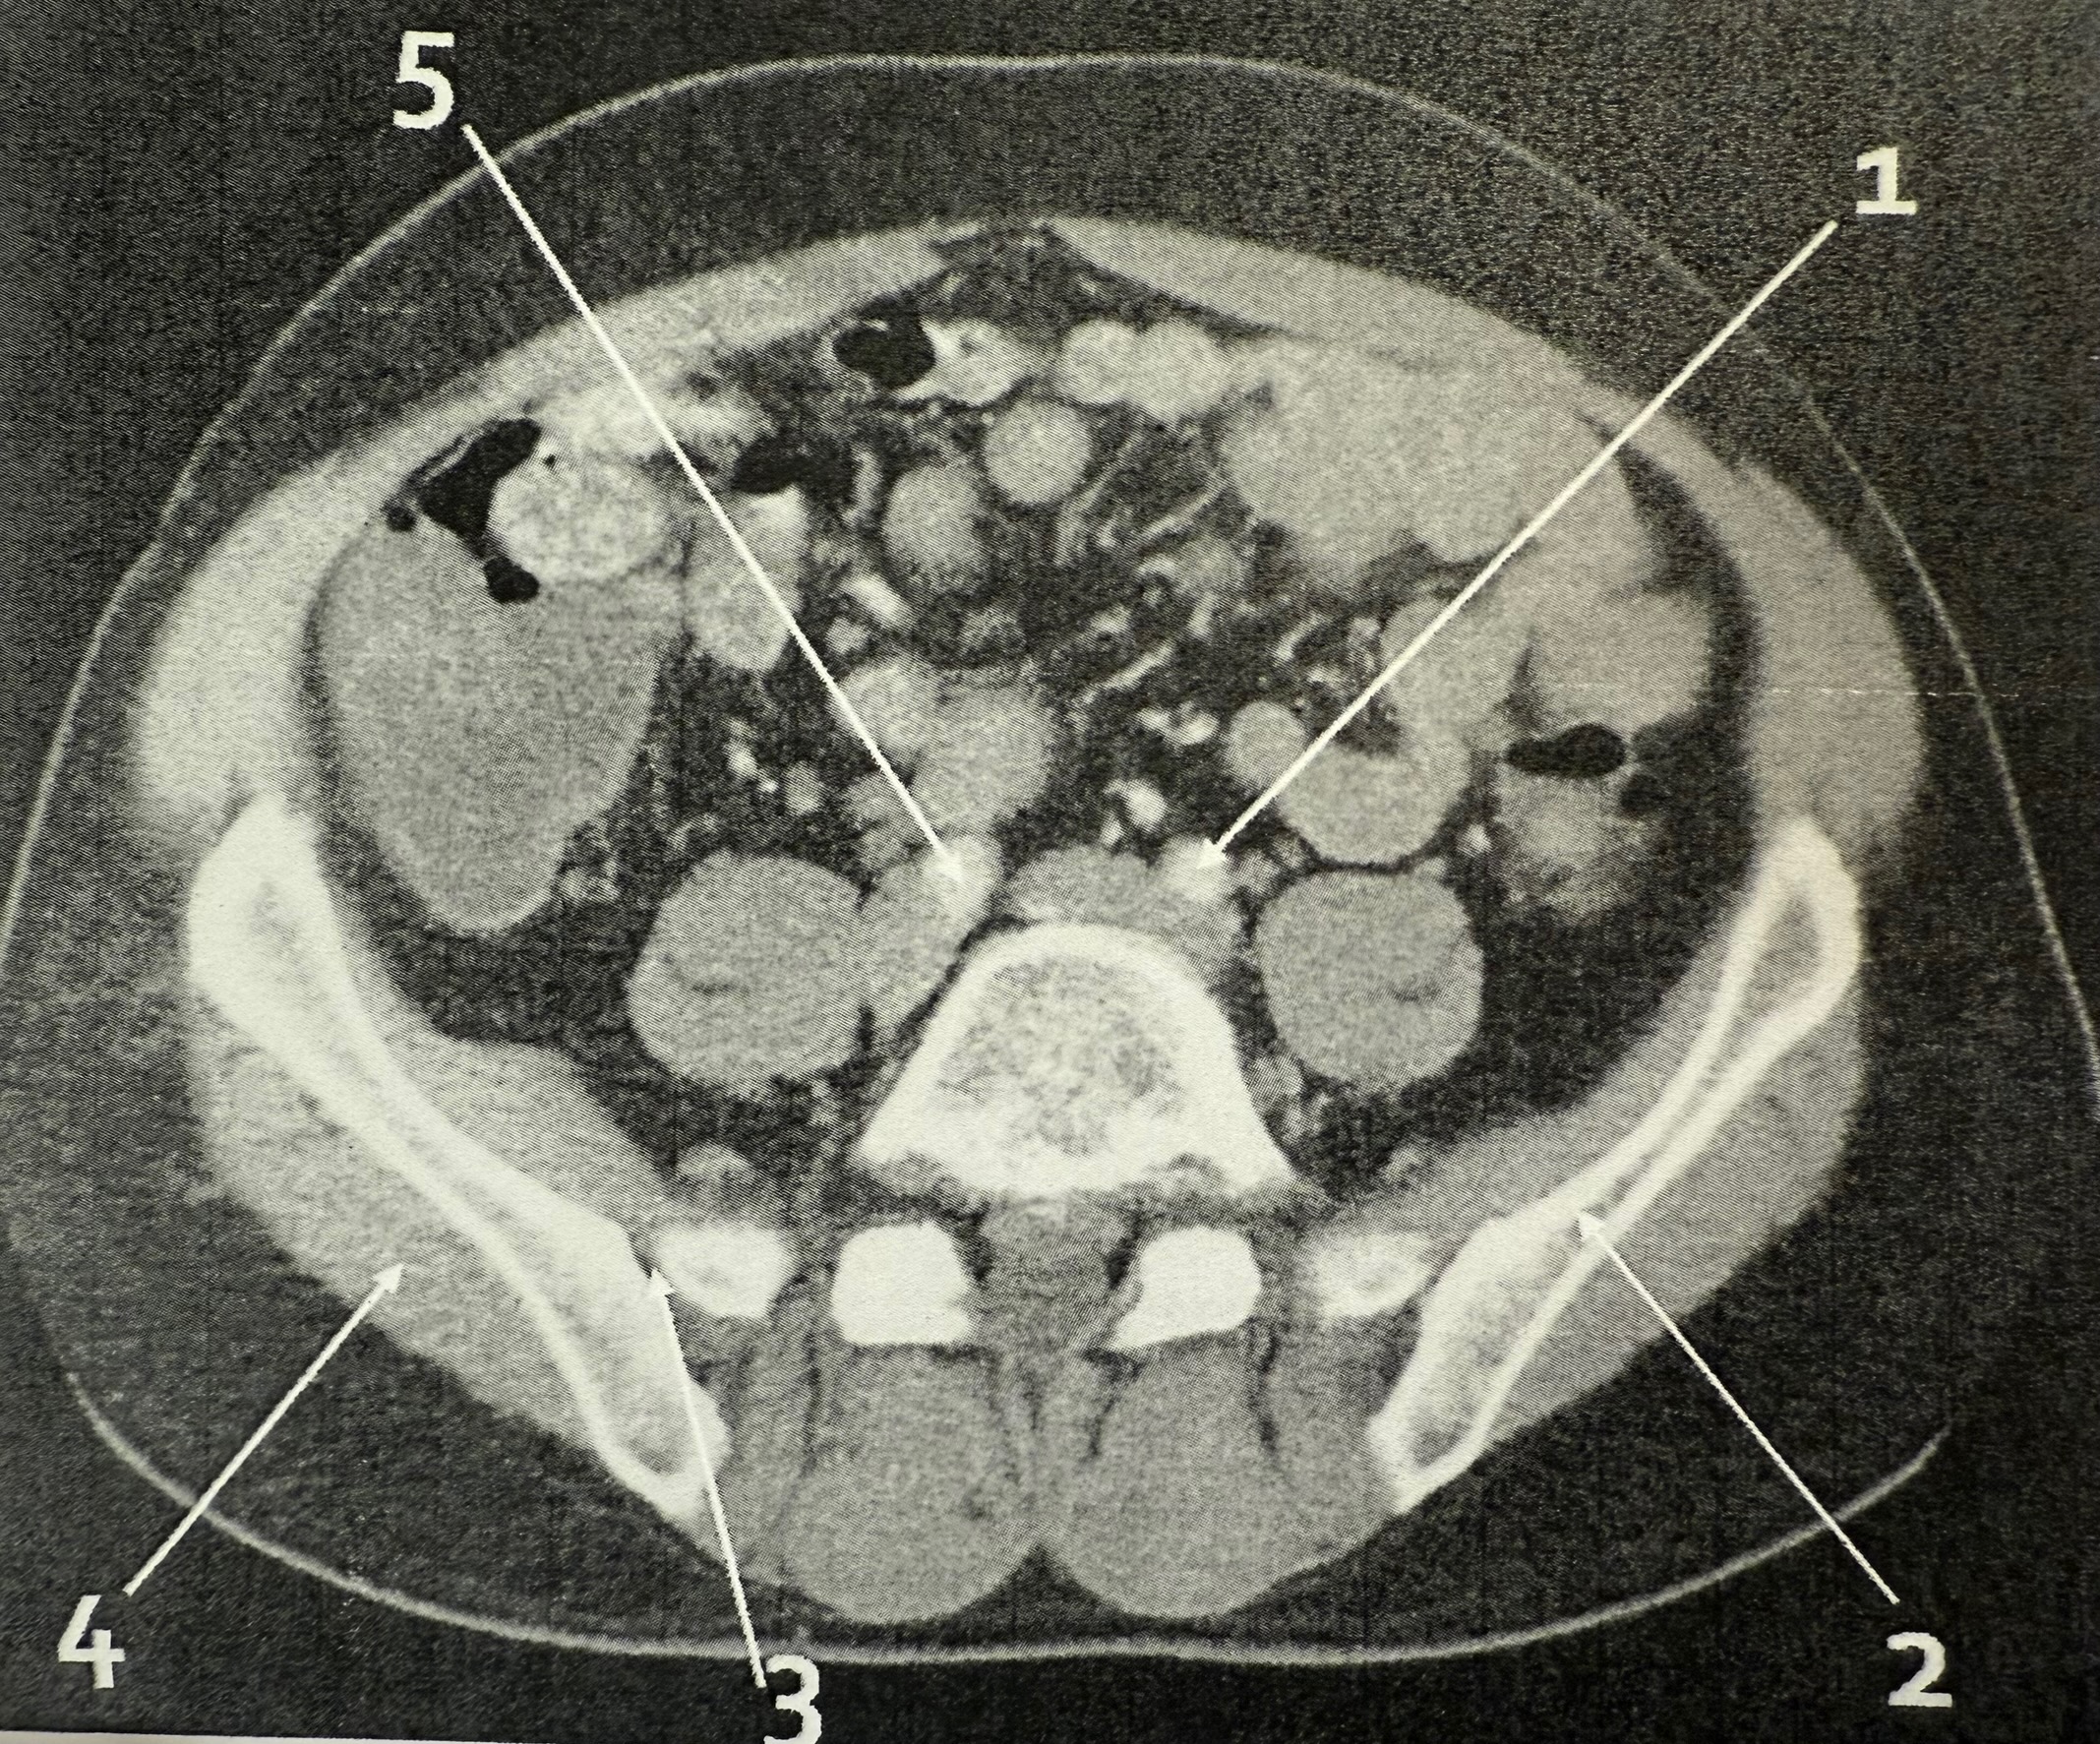

1

common iliac arteries

2

descending colon

5

ascending colon

left common iliac arteries

ilium

3

right sacroiliac (SI) joint

right common iliac artery